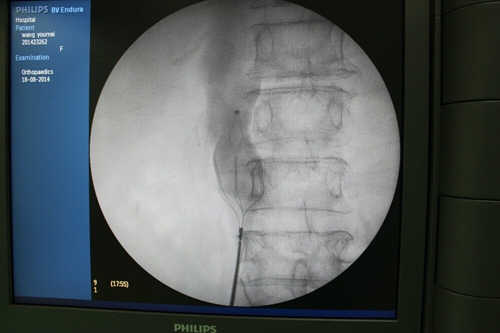

2014年11月13日17:30,南昌大学第二附属医院血管外科主任,全国血管外科学术委员周为民教授到景德镇市第三人民医院骨一科指导开展下肢深静脉血栓微创手术,这是迄今为止,景德镇第三人民医院骨一科开展的第20例血管外科微创手术。

11月13日18:30,手术患者王XX手术结束,安返骨一科病房,刚刚还明显肿胀发亮的右下肢,现在不仅水肿明显消退,肢体温暖,而且足背动脉有明显的搏动。该手术患者来自景德镇市昌江区丽阳乡新建村,如今在景德镇市就可享受省内专家的先进医疗技术,及时避免了可能出现的肺栓塞或截肢等并发症的发生。